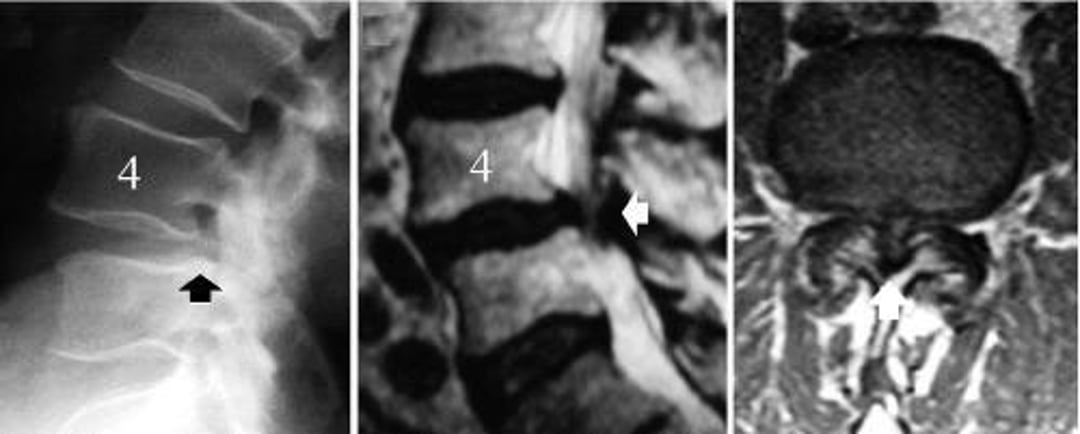

Lumbar Spinal Stenosis Caused by Degenerative Spondylolisthesis of L4-L5

The image on the left is a lateral radiograph of the lumbar spine showing slipping of the L4 vertebra (black arrow—the posterior border of the L5 vertebral body does not align with that of L4). The image in the middle is a midsagittal MRI scan showing compression of the neural structures (white arrow). The image on the right is an axial MRI scan showing severe spinal stenosis at the level of the degenerative spondylolisthesis, L4-5 (white arrow).